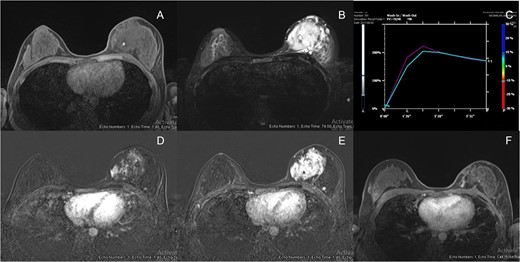

Breast MRI (1.5 T, Espree, Siemens) was performed. It displayed a large infiltrative mass with indistinct margin, approximated ~8.9 × 7.8 × 5.5 cm3. The mass showed isosignal intensity on T1WI and strongly hypersignal intensity on T2WI. After intravenous contrast administration, this mass demonstrated rapid arterial enhancement with mixed plateau and washout on delayed phase (types II and III kinetic curve enhancement pattern). Some areas of the mass showed washout enhancement pattern on delayed phases (type III kinetic curve pattern) but the majority of the mass showed plateau enhancement. This mass extended anteriorly close to the skin without evidence of skin invasion or skin nodules. The mass also contained few small internal hemorrhagic foci (Fig. 3).

(A) Breast MRI showed isosignal intensity in T1WI with hemorrhagic spot (arrow). (B) Breast MRI showed strongly high signal intensity in T2WI. (C) Signal time curve showed type 2 and type 3 kinetic curve pattern but type 2 in majority. (D) Breast MRI showed rapid arterial enhancement in early arterial phase. (E) Breast MRI showed mixed plateau and washout enhancement in delayed phase. (F) Breast MRI post radiation showed interval decreased in size, currently showed slow arterial enhancement with persistent enhancement on delayed phases (type I kinetic).

Preoperative radiation was suggested by our multidisciplinary team. After the external beam irradiation with total dose of 60 Gy in 30 fractions was obtained, the physical examination showed markedly decreased size of the tumour. Follow up mammogram and ultrasound demonstrated an ill-defined mass with interval decreased in size and vascularity. Correspondingly, the follow up MRI showed interval decrease in size and enhancement of a 5.3 × 3.0 cm2. ill-defined infiltrative enhancing mass at left upper inner quadrant. This mass showed slow arterial enhancement with persistent enhancement on delayed phase (type I kinetic curve enhancement pattern) (Fig. 3). The patient had mild erythematous skin after radiation. As a result, breast conserving surgery was suggested by our multidisciplinary team.